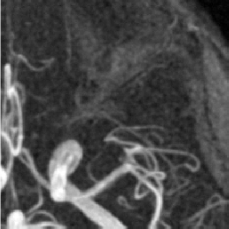

(d) Circle of Willis

Figure 2: Test Images.

We turn now to test TDIHT for high dimensional signals. We test the performance of several MRI images: the Shepp-Logan phantom, FLAIT brain image, T2 Sagittal view of the lumbar spine and the circle of Willis. The first image is of size 256×256256256256\times 256, while the other are of size 512×512512512512\times 512. They are all presented in Fig. 2.

We focus on the recovery of these images from a few number of Fourier measurements. With 𝛀𝛀{\mathbf{\Omega}} set to be the undecimated Haar transform with one level of resolution (redundancy four) and 𝐃𝐃\mathbf{D} its inverse transform, we succeed to recover the phantom image using only 181818 sampled radial lines, which is only 6.5%percent6.56.5\% of the measurements. This number is only slightly larger than the number needed for GAP, relaxed ASP (RASP) and Relaxed ACoSaMP (RACoSaMP) in [10, 38]. The advantage of TDIHT over these methods is its low complexity as it requires applying only 𝐌𝐌{\mathbf{M}} and its conjugate and 𝛀𝛀{\mathbf{\Omega}} and its inverse transform while in the other algorithms a high dimensional least squares minimization problem should be solved. Note also that for AIHT and RAHTP the number of radial lines needed for recovery is 353535 and for IHT (with the decimated Haar operator with one level of resolution) we need more than 505050 radial lines.